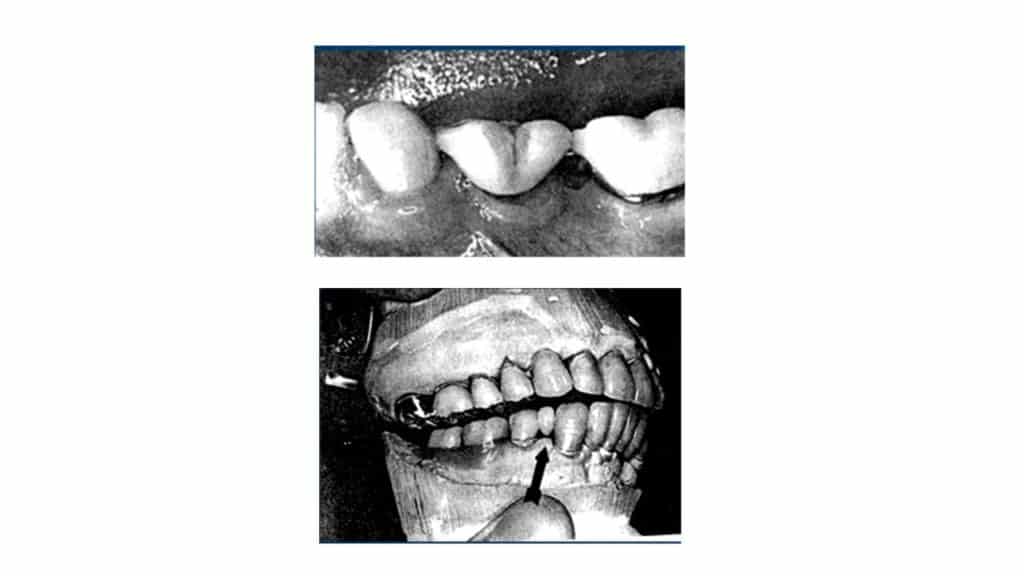

Types Of Pontic Designs . A conventional pontic, a sanitary pontic, and a modified sanitary pontic. Three designs of pontics were tested: Designs (types) of pontic (a) pontics with mucosal contact: It begins with definitions of a pontic and outlines key considerations for pontic design including. Saddle pontic (full ridge lap) overlaps the ridge (largest area of contact). The collective data showed that the most popular pontic design among participant is the ridge lap pontic (69%) followed by modified ridge lap. This document discusses pontic design in fixed partial dentures. Some fixed partial dentures are fabricated entirely of metal, porcelain, or acrylic resin, but most use a.